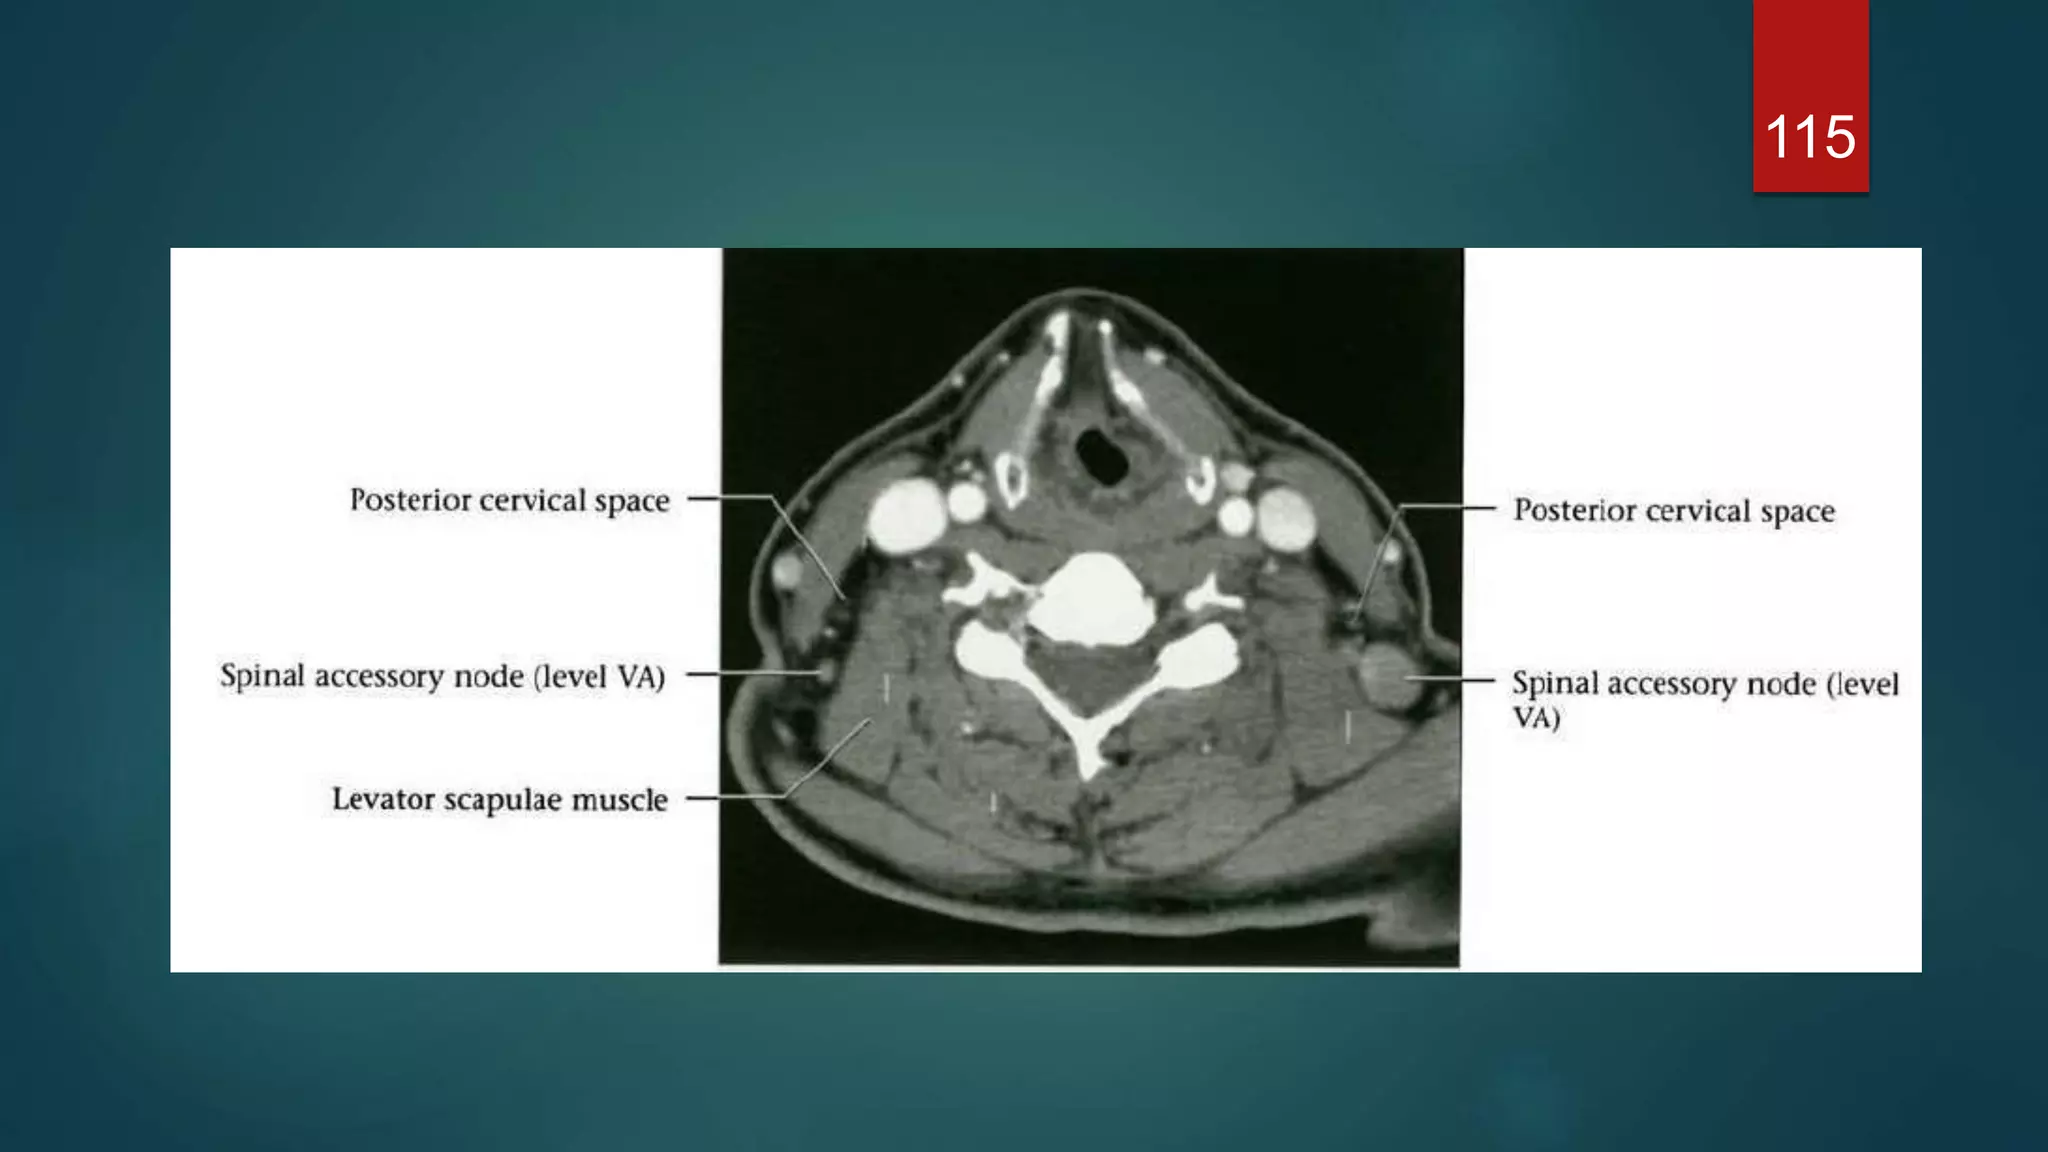

POSTERIOR CERVICAL SPACE : Extend from the skull base to the clavicles.

 Deep and posterior to sternocledomastoid

 Content : fat, spinal accessory nerves and spinal accessory chain of deep cervical lymph

nodes.

115